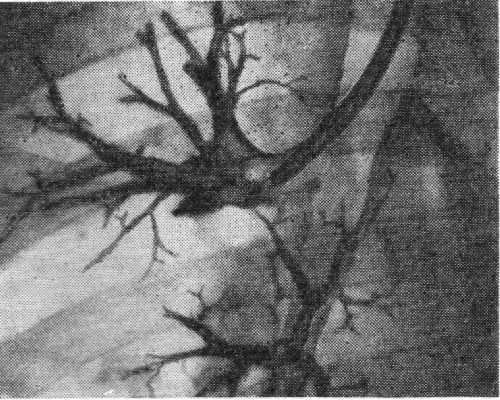

Рис. 2. Катетеры и зонды для бронхографии: 1 — управляемый катетер Розенштрауха; 2 — управляемый катетер Розенштрауха — Смулевича; 3—5 — зонды Метра.

Для прицельного заполнения бронхов применяют специальные наборы полуупругих резиновых зондов, кончики которых изогнуты под различными углами, соответствующими углам отхождения отдельных бронхов (зонды Метра). Шагом вперед явилась идея управляемых с помощью нити катетеров (катетеры Розенштрауха, Розенштрауха — Смулевича), к-рым в нужный момент под рентгеноскопическим контролем можно придать необходимый изгиб (рис. 2). При потягивании за выведенную наружу нитку кончик катетера может быть изогнут и путем вращения направлен в тот или иной бронх (рис. 3). В последние годы в практику входят управляемые катетеры, изготовленные из прозрачных пластических масс, содержащих рентгеноконтрастное вещество, сконцентрированное в виде тонкой нити в стенке катетера.

Среди различных наборов катетеров для прицельной бронхографии (Kassay, Metras, Soulas) и др. наибольшее распространение получили катетеры Метра.

Набор Метра включает шесть полуупругих резиновых катетеров (зондов) с различной формой и кривизной изгиба дистального конца, катетера с надувной резиновой манжеткой, обтурирующей просвет бронха, и металлического гортанного мандрена.

Катетеры изготовлены из рентгеноконтрастной резины. Длина катетера — 450 мм, наружный диаметр — от 4 до 6 мм.

Катетеры Метра проводятся через гортань с помощью мандрена из упругой проволоки, который затем извлекается; введение катетера в бронх осуществляется под рентгенологическим контролем. Недостатком таких катетеров считают необходимость смены их для контрастирования различных бронхов. Поэтому А. Алтыпармаков (1961) рекомендует в некоторых случаях вводить одновременно два или три катетера.

Выбор формы и калибра катетера производится индивидуально, но при этом руководствуются следующими правилами: прямой катетер служит для зондирования базальных сегментарных бронхов нижних долей (7—10); катетер с малым изгибом используется для зондирования среднедолевого и правого верхнедолевого бронхов, «прямо» изогнутый катетер вводится в левый верхнедолевой и верхний сегментарный бронхи нижней доли (6); катетер с наибольшим изгибом служит для зондирования верхушечного сегментарного бронха верхней доли (1); задний и передний сегментарные бронхи (1 и 2) и язычковые бронхи верхней доли левого легкого (4 и 6) зондируются катетерами с двойным изгибом. Детально техника зондирования сегментарных бронхов катетерами Метра изложена в переведенной на русский язык монографии А. Алтыпармакова (1961).